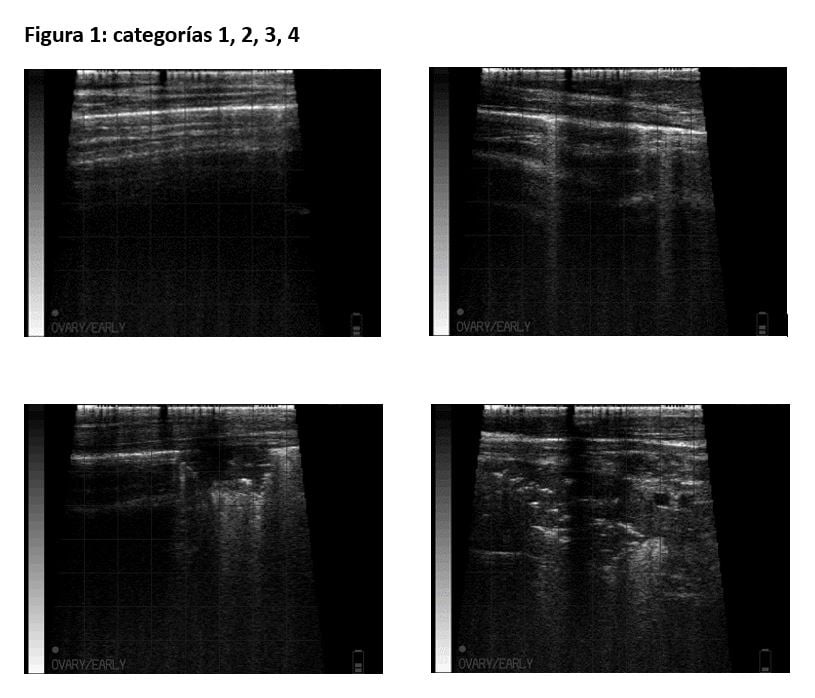

Existen distintas propuestas de clasificación de las lesiones pulmonares en varios puntos (4,12). Sin embargo, se ha optado por establecer únicamente 4 categorías, para simplificar y agilizar el trabajo en granja. Los terneros explorados se clasifican en 4 grados que se definen a continuación (figura 1):

1: Se define como un pulmón con parénquima normal, aireado sin zonas de consolidación.

2: Se define como un pulmón sano pero que presenta artefactos de “cola de cometa” difusos sin consolidación.

3: Se define como un pulmón que presenta lesiones pequeñas y consolidadas en el parénquima.

4: Se define como un pulmón que presenta varias áreas o una muy extensa con consolidación importante.

Los terneros de grado 1 y 2 se consideran sanos, es decir, mamones que no requieren tratamiento. Por el contrario, los mamones clasificados como grado 3 y 4 son terneros que presentan neumonía moderada y severa, respectivamente.